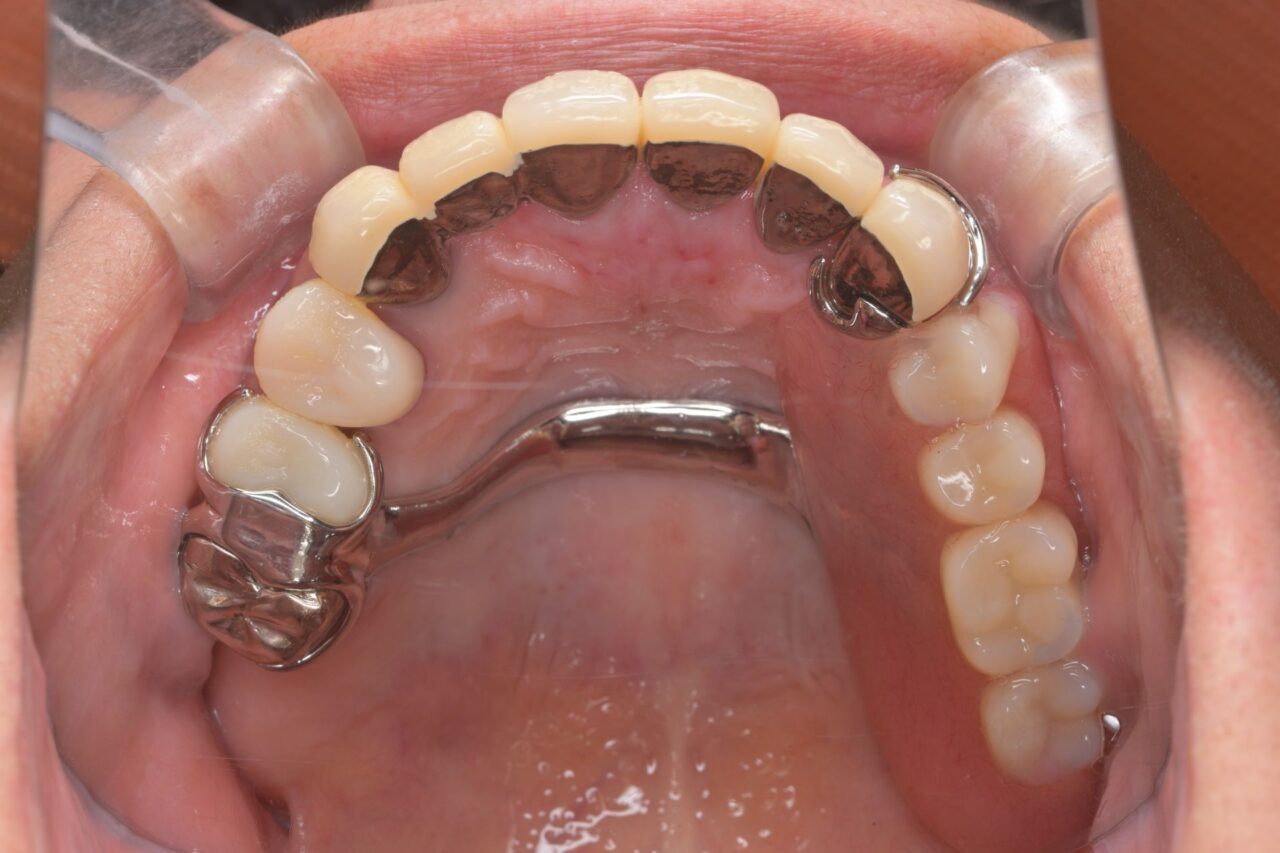

上面

歯が無い部分は入れ歯で補いました。

左右の入れ歯を金属でつないで強固にしています。はじめは舌感が悪いと思いますが、慣れが必要です。